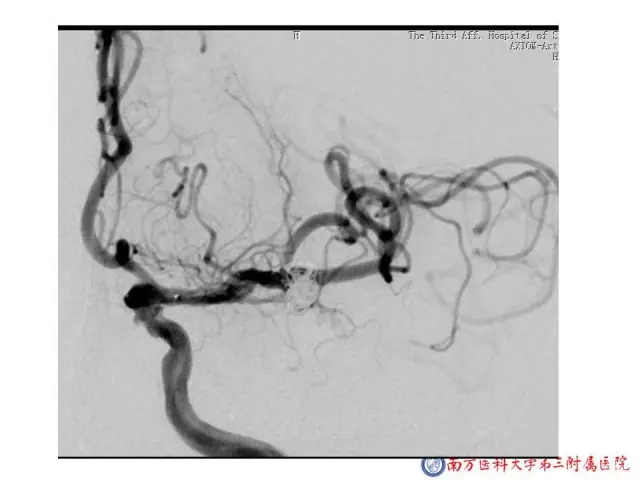

今天为大家分享的是“强生医疗CNV-神经介入专栏”第二十五期,由南方医科大学第三附属医院神经外科主任黄理金教授带来的“Enterprise支架辅助栓塞动脉瘤的优势”精彩讲课视频及PPT,欢迎观看。文章仅代表作者个人观点,如有不同见解,欢迎同道斧正!